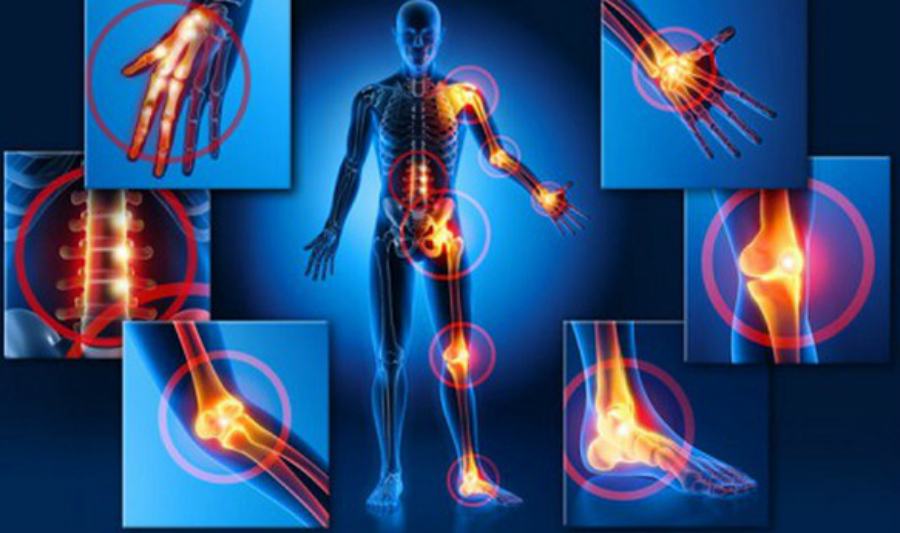

COSENZA – Prosegue nella città calabrese la seconda edizione della campagna nazionale “Malattie Reumatologiche? No grazie!” promossa dalla Società Italiana di Reumatologia (SIR). Incontri informativi on line dedicati agli over 65. L’obiettivo dell’iniziativa è far comprende a tutti gli italiani, non più giovanissimi, la gravità di queste patologie. “Sono malattie serie, molto dolorose, potenzialmente invalidanti e che risultano in crescita nel nostro Paese – afferma il dott. Maurizio Caminiti, Reumatologo, Direttore Reumatologia e Centro Osteoporosi Grande Ospedale Metropolitano Bianchi Melacrino Morelli, Reggio Calabria e relatore dell’incontro -. Colpiscono più di 5 milioni di italiani e sono ancora in larga parte sottovalutate dalla popolazione. Non possono essere considerate patologie esclusivamente della terza età anche se gli anziani sono particolarmente esposti.

Si calcola che in Italia circa un terzo degli over 65 usa regolarmente farmaci antinfiammatori ed antireumatici per il trattamento di artriti e artrosi. Il 25% invece assume vitamina D per contrastare l’osteoporosi. Nonostante la pandemia abbiamo deciso di proseguire con la nostra campagna – continua il dott. Caminiti -. Bisogna creare nel nostro Paese una nuova cultura della prevenzione e per questo durante gli incontri ribadiremo l’importanza di seguire, anche durante la terza età, stili di vita sani. E’ anche assolutamente necessario segnalare tempestivamente i sintomi delle patologie reumatologiche al proprio medico per poter ricevere un intervento terapeutico adeguato”. La campagna prevede 50 incontri virtuali ed è realizzata grazie al contributo non condizionante di Sanofi Genzyme e MSD Italia.